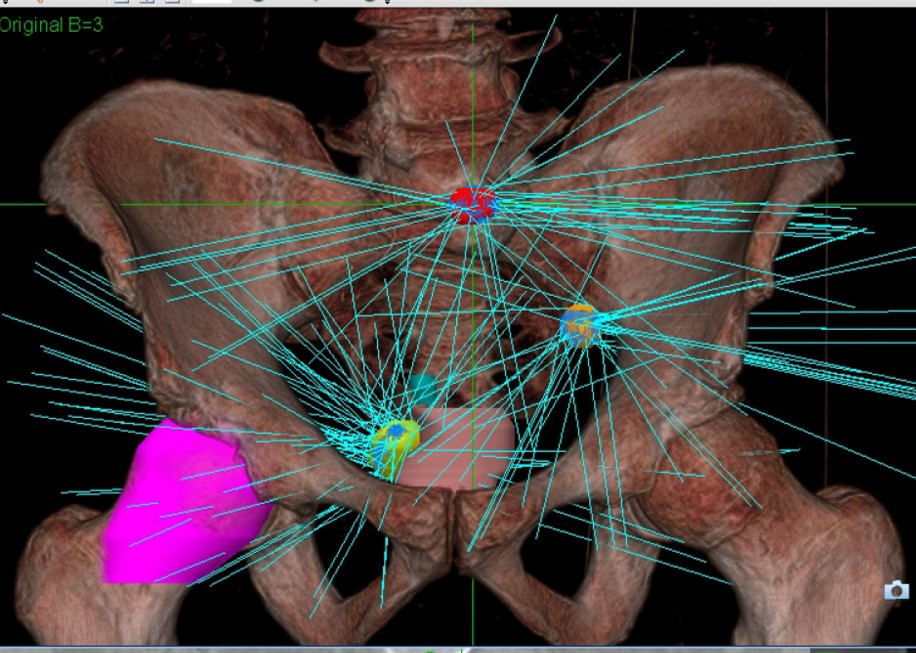

TIROG physicians have access to an Accuray Cyberknife at the Seattle Radiosurgery Center, the only CyberKnife in the Seattle metropolitan area. The CyberKnife is the world's first and only robotic radiosurgery system. The CyberKnife can allow for radiosurgery treatment throughout the body. This can be particularly useful for inoperable or surgically complex tumors. One of the revolutionary advances in CyberKnife treatment lies in the ability to take real-time x-ray images of the treated area and adapt the treatment in real-time. Often, your physician will have three gold 'seeds' or beads placed in or near a tumor. The machine can see these beads move (for example when you are breathing), and the robotic arm can compensate for this motion, moving with you. This allows for precise radiation treatment in moving tumors, such as lung tumors or prostate cancer. For more information, please see http://www.swedish.org/services/radiosurgery-center.